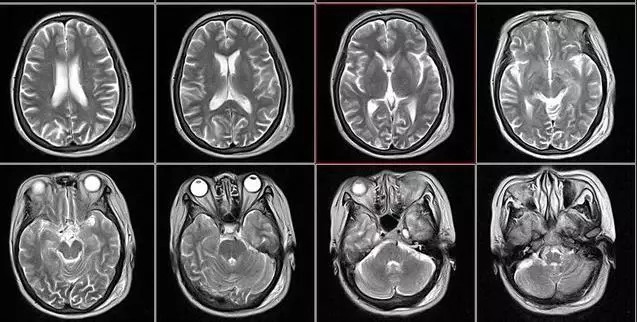

核磁共振

摇一摇再看

核磁共振机使用较强大的磁场,使人体中所有水分子磁场的磁力线方向一致,这时磁共振机的磁场突然消失,身体中水分子的磁力线方向,突然恢复到原来随意排列的状态。

简单说,就相当于用手摇一摇,让水分子振动起来,再平静下来,感受一下里面的振动。所以,核磁共振也被戏说为是摇摇看的检查。

颈椎腰椎——最佳选核磁,次选CT

颈椎病、腰椎间盘突出等椎间盘疾病需要观察椎间盘与相应的神经根,要想更好观察这些软组织,最优选择就是核磁。同样,对于关节、肌肉、脂肪组织检查,核磁也是首选。